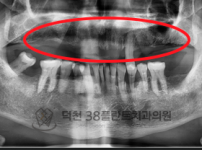

치료전후